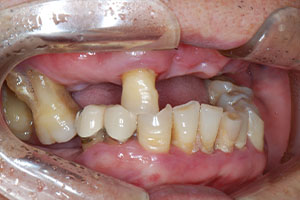

치료증례 전후사진

Before & After